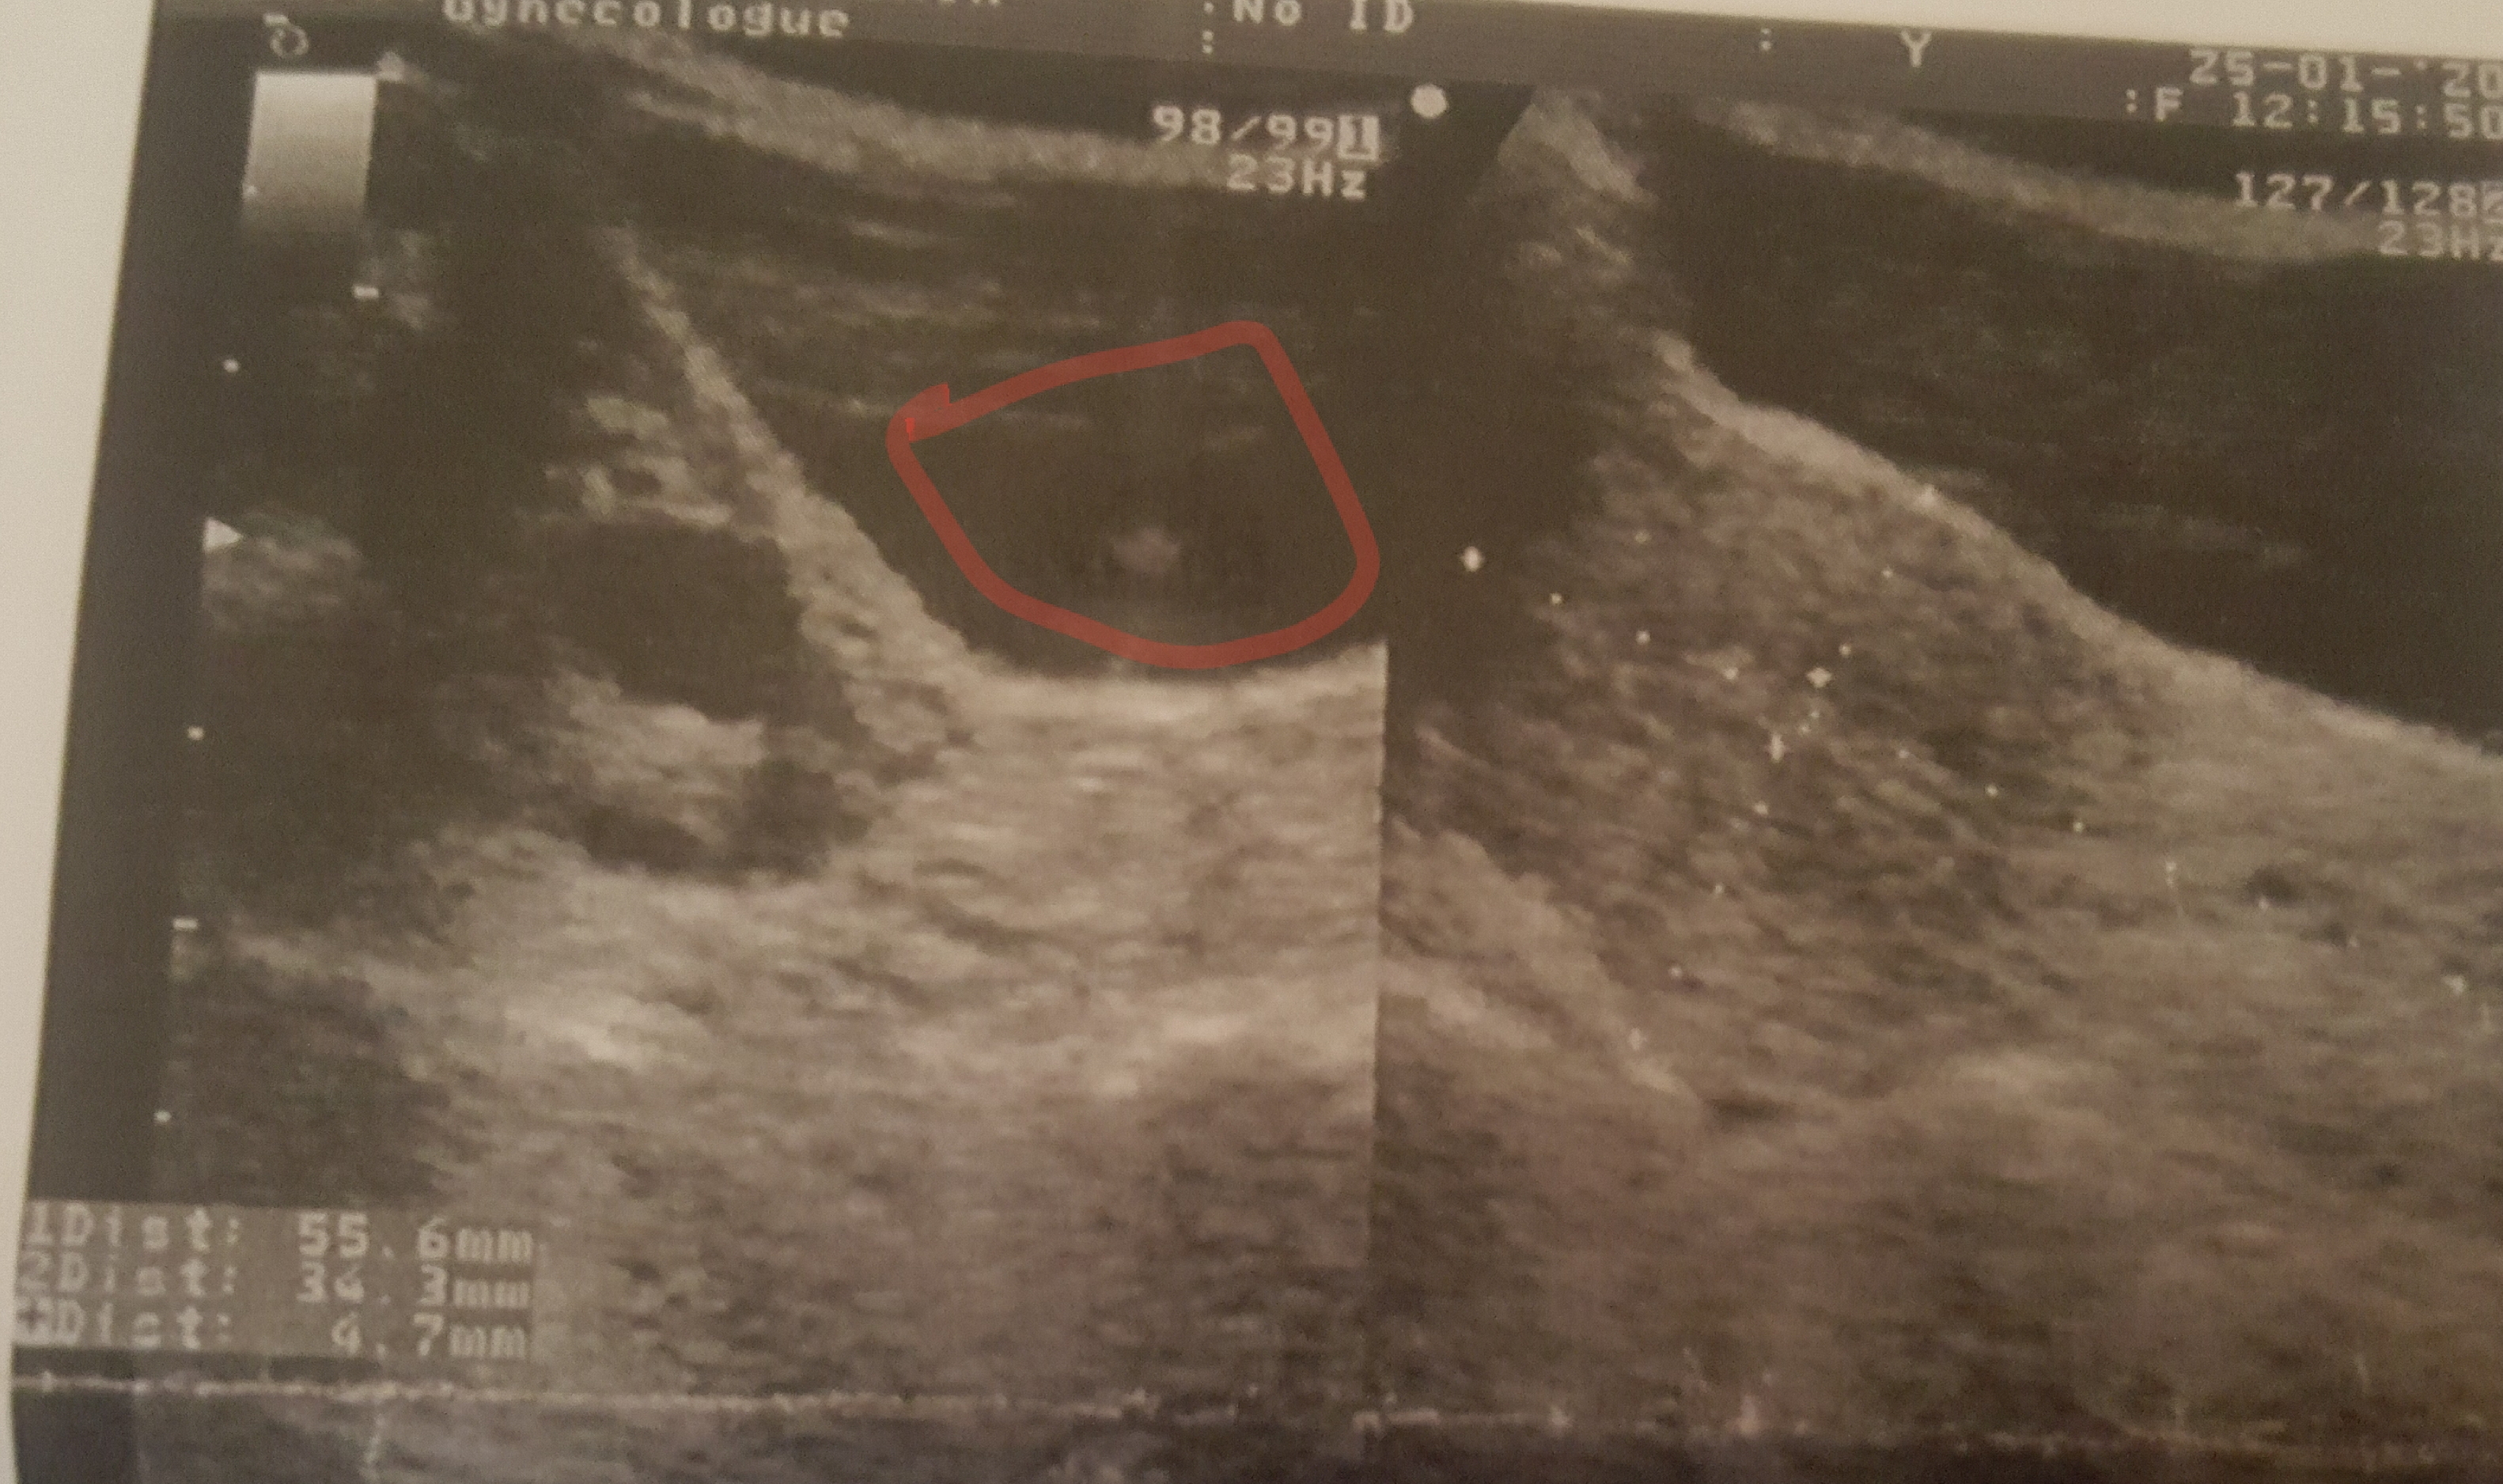

لدي ألم اسفل البطن و اسفل الظهر منذ شهر و يوم الدورة الشهرية اتت عبارة عن بقع سوداء عملت تحليل...